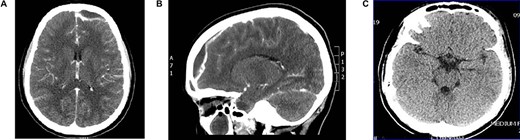

Young man referred as a case of frontal lobe abscess as a complication of untreated frontal sinusitis. The patient presented with fever, headache and changes in personality and mood. Coronal MRI brain (Fig. 4A) showed a large frontal lobe abscess and an inflamed frontal sinusitis as in Fig. 4B. the patient was managed with a combination of intravenous antibiotics, endoscopic frontal drainage and frontal craniotomy to drain the frontal abscess by the neurosurgery team. Patient tolerated the procedures well with no complications as shown in postoperative CT brain (Fig. 4C).

(A) Preoperation coronal MRI brain with large frontal lobe abscess, (B) preoperation sagittal MRI of frontal lobe abscess extending from inflamed frontal sinus and (C) post drainage CT brain showing complete resolution of the frontal abscess.